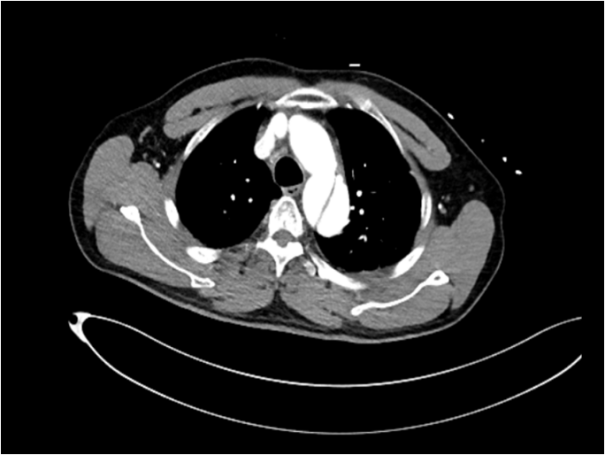

时间就是生命。医生会结合症状,快速进行以下检查:医院会根据CT血管成像(CTA)进行诊断。如确诊为主动脉夹层,则会进行紧急处理,立即镇痛、控制血压和心率(如静脉注射β受体阻滞剂)。

主动脉腔内修复术:微创治疗。通过大腿根部的股动脉,将一个覆膜支架送入主动脉夹层部位,像打补丁一样覆盖住内膜破口,使血流不再进入假腔,促进假腔血栓化愈合。